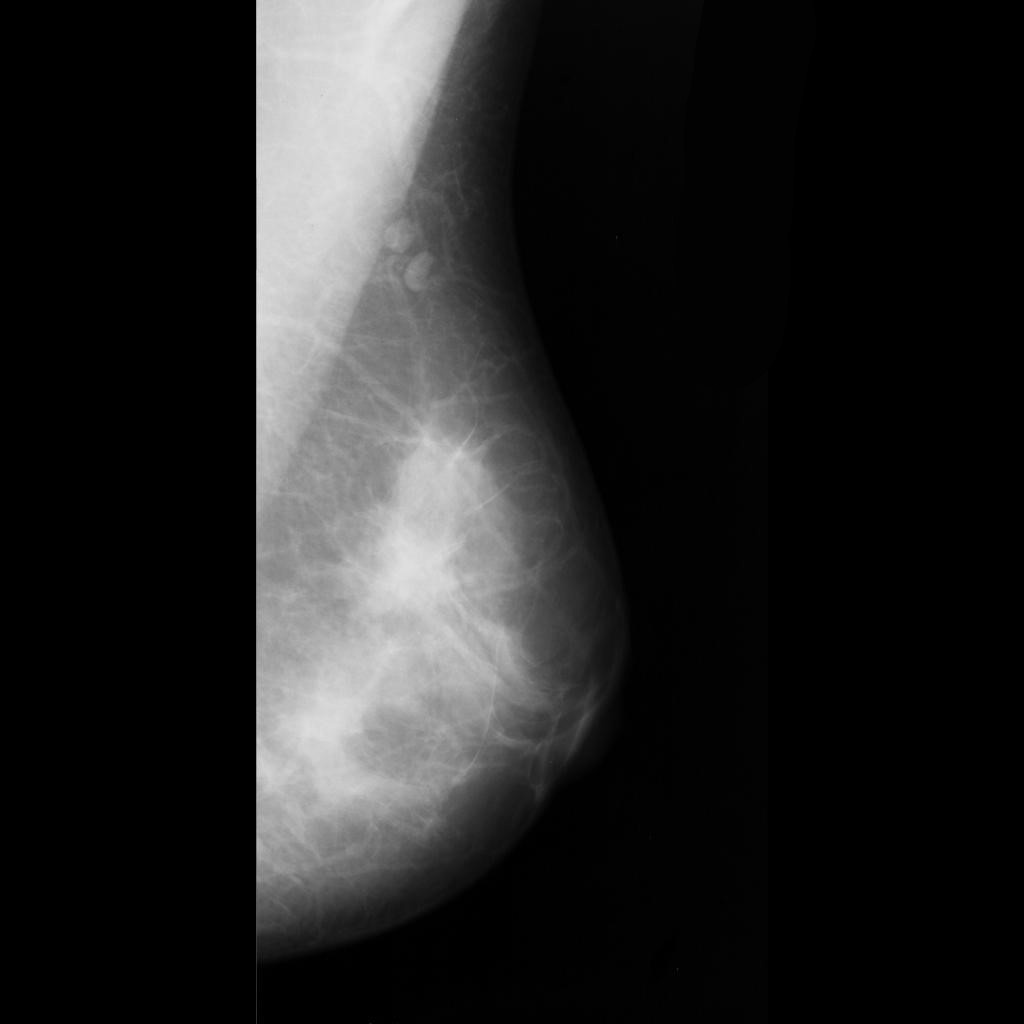

malignant